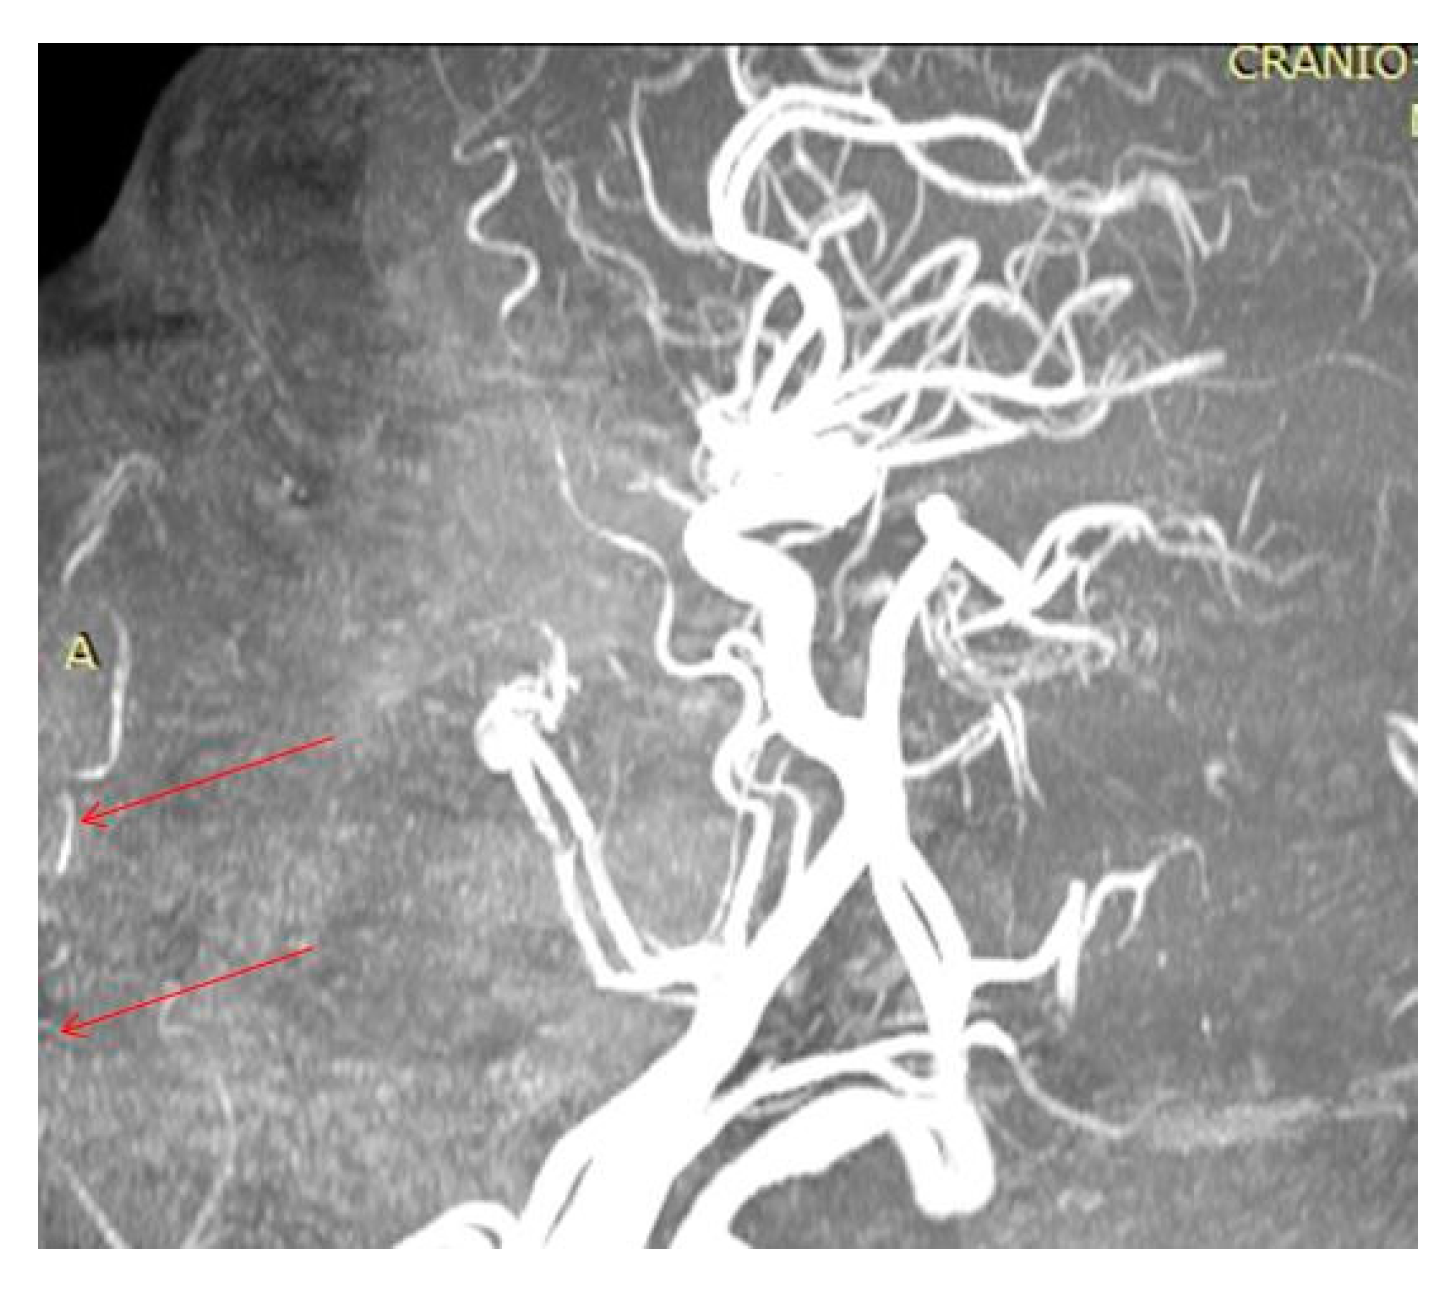

In the oral region, at the level of the lips, the main vascularization sources were objectified—branches from the facial artery (Figure 4). These blood vessels cross the labial SMAS layer and distribute to the skin and mucosa at this level.

Figure 4. Identification of the superior (superior red arrow) and inferior (inferior red arrow) labial branches of the facial artery (A).